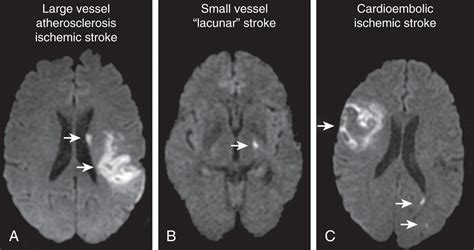

Differentiating Stroke Types

Another critical role of the CT scan is distinguishing between an ischemic stroke and a hemorrhagic stroke . A hemorrhagic stroke will show up as a bright area on the CT scan, indicating bleeding in the brain. For ischemic strokes, the scan will often initially appear normal or show the subtle signs mentioned above. This difference is super important because treatments vary dramatically. If the CT scan shows bleeding, clot-busting drugs are usually not an option. Instead, the focus is on controlling the bleeding and managing the pressure in the brain.

• MRI (Magnetic Resonance Imaging): An MRI can provide even more detailed images of the brain and may be used in cases where the CT scan is unclear or to assess the full extent of the damage. An MRI is better for detecting early changes in the brain tissue.